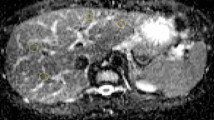

Table 1 presents the SNR values obtained by each scanner at both positions for each slice thickness. SNRs were roughly 2–3 times higher in the 3.0-T scanner than those in the 1.5-T scanner. Peripheral SNRs were approximately 1.2–1.5 times higher than those at the center. Furthermore, SNRs at b = 0 were approximately three times higher than those at b = 1000. Figure 3a, b shows the mean ADC derived from each slice thickness using the 1.5-T and 3.0-T scanners, respectively. The average ADCs at 1.5 T and 3.0 T were 1.092 × 10−3 mm2/s (range 1.075–1.101 × 10−3 mm2/s) and 1.120 × 10−3 mm2/s (range 1.113–1.127 × 10−3 mm2/s), respectively. On an average, the ADC at 3.0 T was approximately 2.0% higher than that of water at 0 °C (P < 0.001 for all slice thicknesses).

Apparent diffusion coefficient (ADC) plots obtained using the 1.5 T scanner (a) and 3.0 T scanner (b). The black dots and error bars show the average and 95% confidence intervals, respectively, calculated from five consecutive image acquisitions. The ACDs at the peripheral positions are merged from all four rods. The transverse dashed and dotted lines in each graph represent 1.1 × 10−3 mm2/s (the ADC of water) and 3.0 deviations from 1.1 × 10−3 mm2/s. The solid line in each graph represents the average ADC at each scanner. The asterisk indicates that there is a statistically significant difference between the measured ADC and the ADC of water (1.1 × 10−3 mm2/s). Previous research has indicated that the ADC deviations are within ± 3.0% near the magnet center using different scanners [4]. There was no obvious underestimation of the ADC values at either position on the 1.5 T and 3.0 T scanners. The ADCs obtained using the 3.0 T scanner show systematic variation from the ADC value of water (P < 0.001); however, all ADC values were still within 3.0%